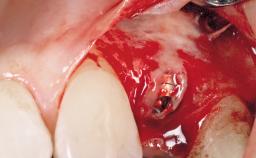

Implant Placement with Simultaneous Contour Augmentation using GBR

Surgical treatment of a 67-year-old male patient exhibiting an extended edentulous space in the anterior maxilla after the removal of three hopeless incisor teeth.

The video demonstrates implant placement using a surgical stent according to the principle of prosthodontically driven implant placement. The deficient ridge is augmented with locally harvested autologous bone chips, a superficial layer of xenogenic DBBM particles and a resorbable collagen membrane. The surgery is completed with a precise, tension-free primary wound closure.